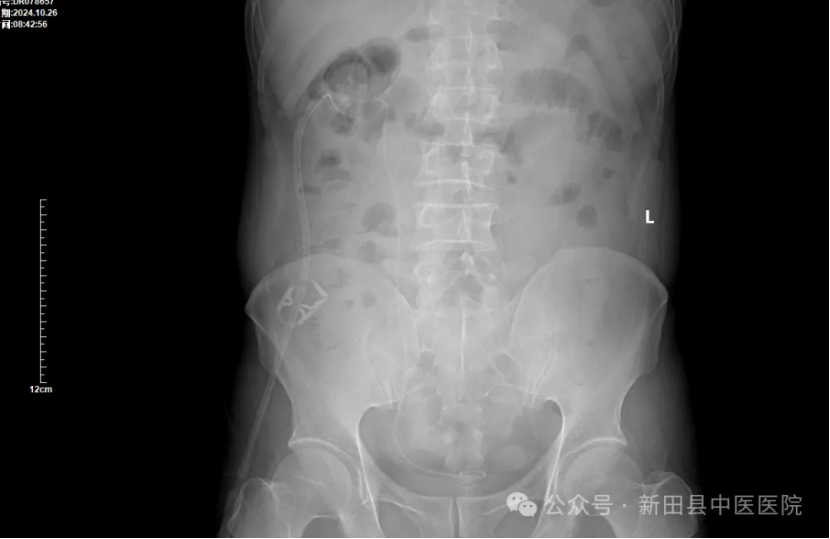

▲术前DR